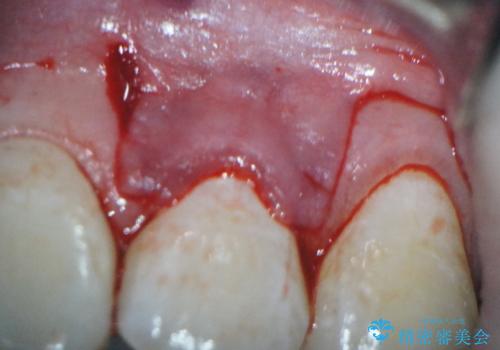

前歯の歯肉退縮 歯周形成外科(歯冠側移動術)

- 上顎左側側切歯の歯肉退縮を主訴に来院されました。

生活に支障はないが審美的要求が強く歯肉形成外科(歯冠側移動術)を行うこととしました。

根面被覆術には結合組織を用いる場合もありますが、今回のケースでは、角化歯肉が十分あり、審美性の要件が強いため、隣在歯との調和が取りやすい歯冠側移動術のみで対応しております。